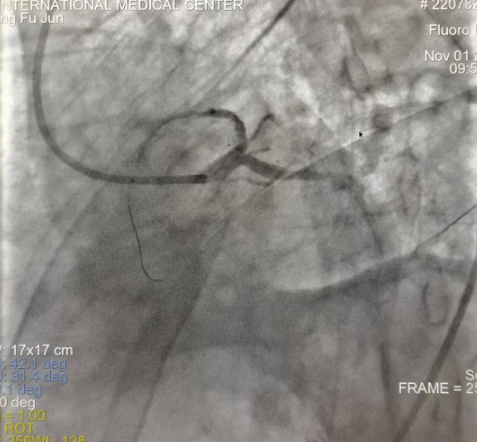

閉塞的血管再通時間取決于急救時長、轉(zhuǎn)運時長和治療時長,在前兩方面,醫(yī)院已為患者爭取了最短時間?;颊呒覍龠h在陜北,雖然已在趕來的路上,但最快抵達西安也要3小時,在與患者家屬電話溝通同意急診手術(shù)后,醫(yī)療總值班代家屬簽字,康曉軍在請示心臟病醫(yī)院王海昌院長及心臟內(nèi)科CCU尚福軍主任后,積極進行術(shù)前準(zhǔn)備。在沒有家屬陪同、沒有交費、沒有辦入院手續(xù)的情況下,患者經(jīng)胸痛中心綠色通道被送往心臟冠脈介入手術(shù)室,打通了完全閉塞的心臟前降支近段血管。